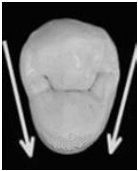

Observe a imagem a seguir:

As setas na imagem representam as faces: